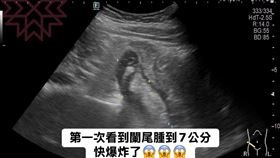

40歲女胃劇烈疼痛!醫驚:闌尾腫了7公分

胃痛絕不能忽視!禾馨民權健康管理診所院長林相宏表示,...